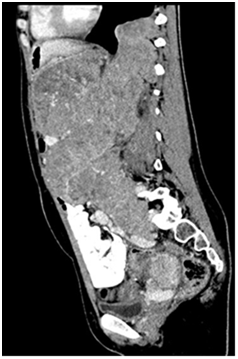

She was subsequently therefore switched to mToR (mammalian target of Rapamycin) inhibitor Evrolimus.5 She showed a good clinical response with improvement in appetite, reduction in pain and requirement of analgesia, better performance status and feeling of general wellbeing. A repeat CT scan after 4 months of treatment revealed that the mass showed reduction in size and there were prominent necrotic appearing areas. The patient remained stable and responding for seven months after being put on mToR inhibitors. On one of the further follow ups she complained of breathlessness and exertional fatigue. She had clinical signs of pleural effusion, which was confirmed on chest radiograph. She was initially managed conservatively but she continued to show clinical worsening requiring a chest tube drainage followed by Pleruodesis. A repeat CT-scan (Figure 3) revealed gross progression of the primary tumor.

Figure 3 Showing gross progression of the lesion.